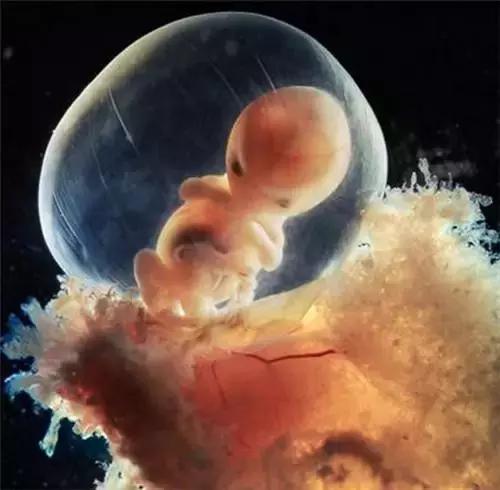

瑞士著名摄影师Lennart Nilsson利用内窥镜可观察到胎囊内部从而获得更加精准绝美的照片。...

瑞士著名摄影师Lennart Nilsson利用内窥镜可观察到胎囊内部从而获得更加精准绝美的照片。Nilsson将光导管与内窥镜相机连接,拍摄出数千张子宫内胎儿的照片,他灵巧的双手创造出了一个奇迹,向全世界展示了人类生命诞生的奥妙。

5周大的胎儿。此时胎儿只有大约9毫米长,面部正在发育,嘴巴、鼻孔和眼睛正在形成